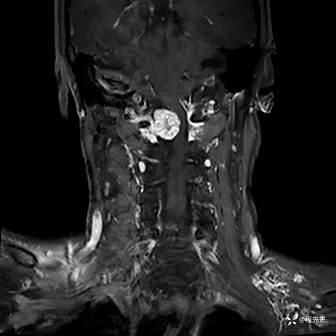

MRI平扫+增强:

T1: